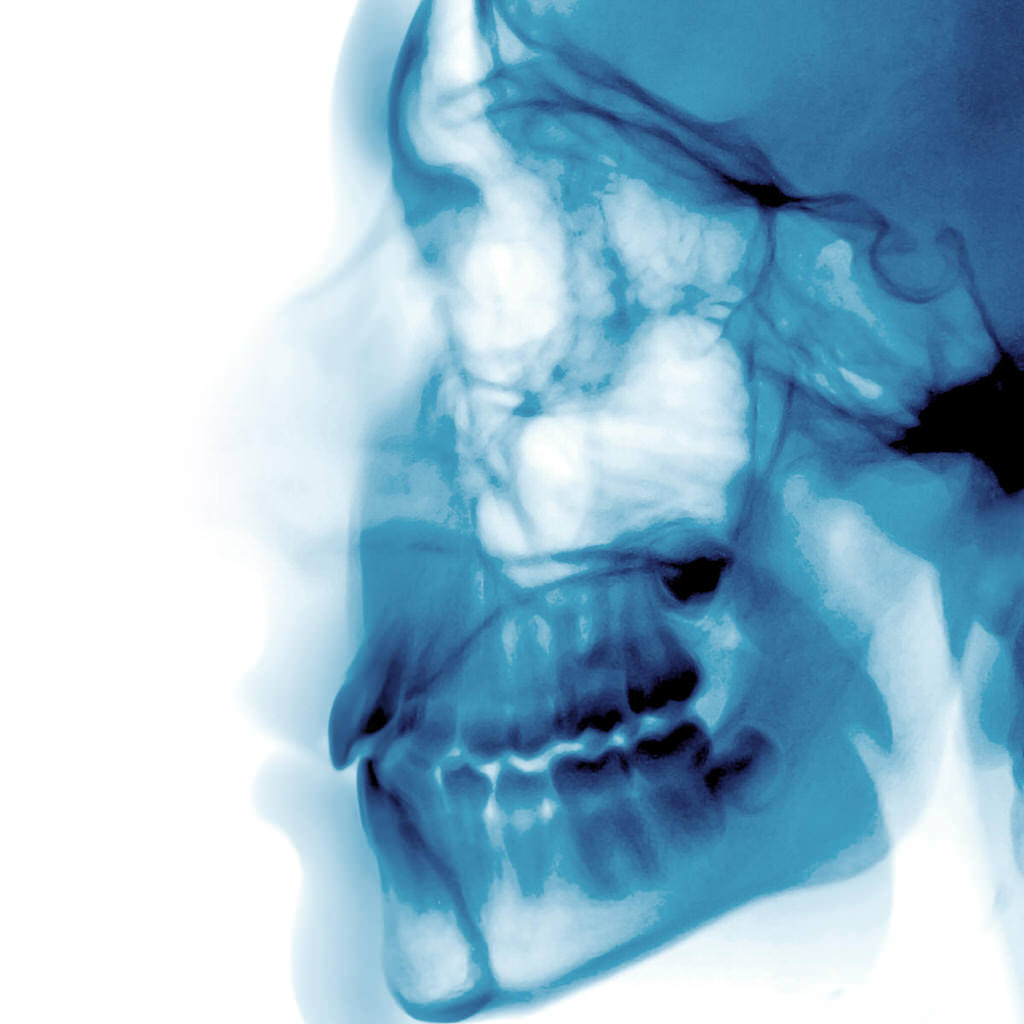

Bei „harmlosem“ Schnarchen und bei leicht bis mittelgradiger Schlafapnoe (Schnarchen mit Atemaussetzern) kann im Rahmen einer Schnarchtherapie eine Unterkiefer-Protrusionsschiene (TAP®-Schiene) eingesetzt werden.

Betroffene nehmen ihr Schnarchen selbst gar nicht oder nur unterschwellig wahr. Tagesmüdigkeit und ein trockener Mund am Morgen sind ein Indiz für das nächtliche Schnarchen. Besonders betroffen ist der Mitschläfer. Eine Schlafapnoe kann gefährliche Auswirkungen wie Bluthochdruck, erhöhtes Herzinfarkt- und Schlaganfallrisiko, Sekundenschlaf am Tage (z.B. beim Autofahren), Depression und gestörte Sexualität haben. Im Schlaf erschlafft die Muskulatur im Rachenraum. Es kommt zum Vibrieren der weichen Gaumenanteile, die Zunge fällt zurück, und es kommt zur Einengung der Atemwege. Mit der Unterkiefer-Protrusionsschiene wird der Unterkiefer vorn gehalten, so dass die Luftwege freibleiben.